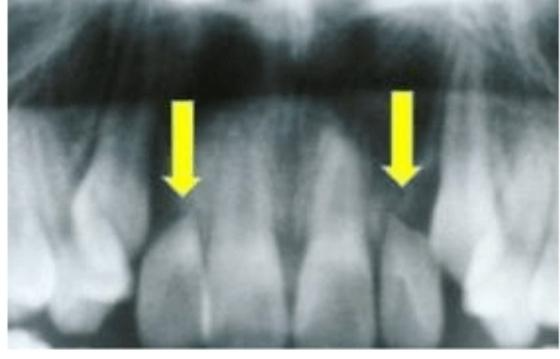

2. 치근 흡수

치아의 뿌리 부분이 뼈 속을 이동하는 동안 약간 짧아지는 현상으로

정도의 차이는 있지만 교정치료를 받은 사람에게서 종종 발견됩니다.

일반적으로 흡수 정도는 경미한 편이지만,

경우에 따라서는 교정치료를 중단하고 신경치료를 진행해야 할 수도 있습니다.

미약한 치근 흡수는 문제없으나

교정치료 중에는 6개월마다 정기적으로 x-ray를 촬영해

치근 흡수 여부를 확인하면서 치료를 진행해야 합니다.